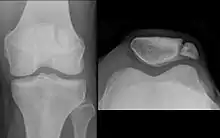

صورة بالأشعة لمريض مع خلع الرضفة. عادة ماتبرز الرضفة على الجزء البعيد لعظم الفخذ.